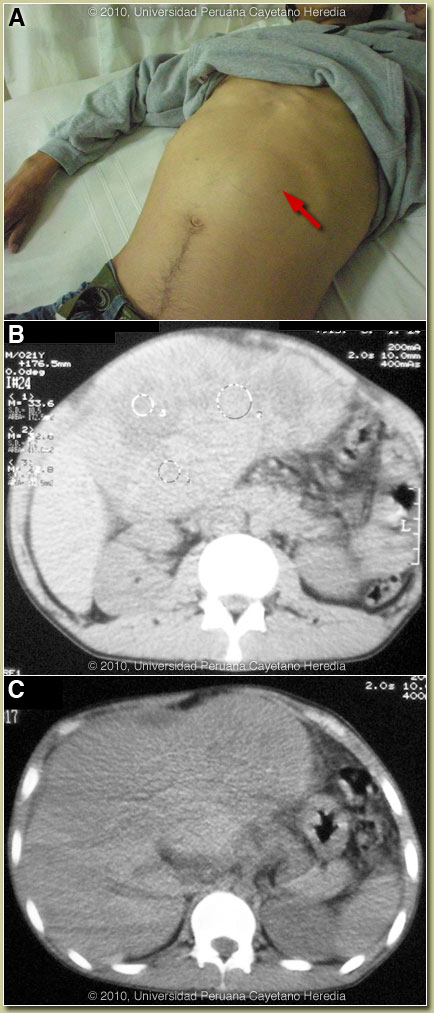

| Diagnosis: Chronic Hepatitis B infection complicated by hepatocellular carcinoma. |

Discussion: A liver biopsy was diagnostic of hepatocellular carcinoma [Images D & E show histology from a similar patient from our files]. Alfa fetoprotein was > 400,000 nanograms/ml. Hepatitis B surface antigen positive; Hepatitis B IgG core antibody (anti HBc) positive. Mother negative for HbSAg.